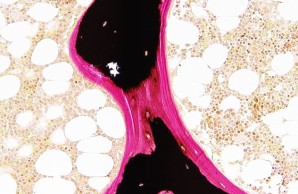

Project 4: Molecular bases of non-classical osteogenesis imperfecta

Project 8: Molecular understanding of fracture healing in early-onset low BMD disorders

Project 8 is investigating the extent to which specific gene variants influence the multi-stage process of fracture healing at the cellular and molecular level. In addition to genetic, metabolic and immunological aspects, the suitability of specific pharmacological interventions to improve bone regeneration is also being analyzed.

Project 9: Impact of specific gene variants on growth plate and articular cartilage in early-onset low BMD disorders

Project 9 covers the characterization of patients who suffer from skeletal dysplasia and/or osteoarthritis in addition to an early-onset low bone mineral density. To investigate the underlying pathomechanisms, histomorphometric and molecular analyses as well as disease modeling using pluripotent stem cells and mouse models are employed.